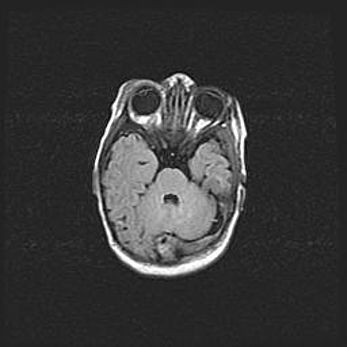

Аномалия Денди-Уокера. Признаки гипоплазии мозолистого тела.

Возраст: 5 месяцев 3 дня

Вес: 5550 г

Пол: мужской

Окружность головы: 39 см

Срок гестации: 40 недель

Аномалия Денди-Уокера – это порок развития головного мозга, для которого характерна триада симптомов: гипотрофия или аплазия червя мозжечка и/или полушарий мозжечка, расширение четвёртого желудочка с формированием ликворной кисты задней черепной ямки, гипертензионная гидроцефалия различной степени.

Гипоплазия мозолистого тела относится к дефектам внутриутробного этапа развития мозговой ткани, возникающим в процессе закладки структур головного мозга, что происходит на начальных этапах развития эмбриона.